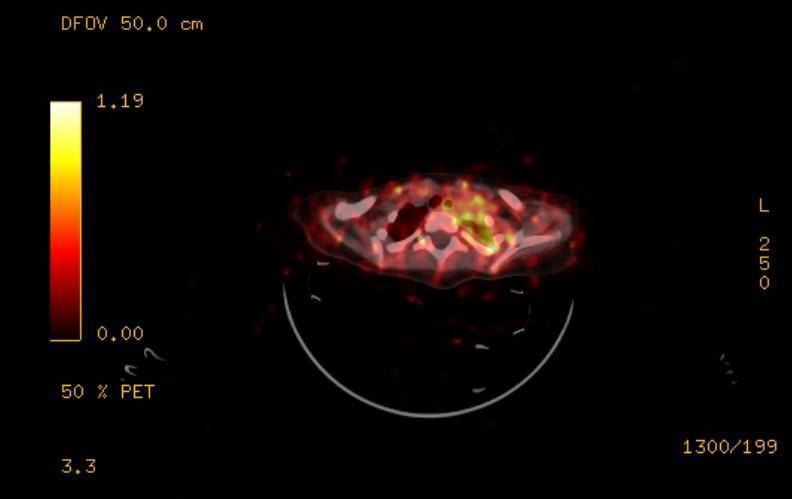

Figure 5: PET-CT showing residual soft tissue in the left superior thoracic aperture above the first rib.

The 20 days after the intervention follow-up of the patient examined levels of Neuron-specific enolase 55,27μg/L (reference level 16,3μg/L) and revealed normal hematology results. The DNA analysis of the tumor material does not show any amplification of MYCN gene. PET-CT conducted one month after the surgery revealed evidence of residual soft tissue in the left superior thoracic aperture above the first rib, probably encasing the sympathetic nerves (Figure 5). This imposed the implementation of chemotherapy courses.